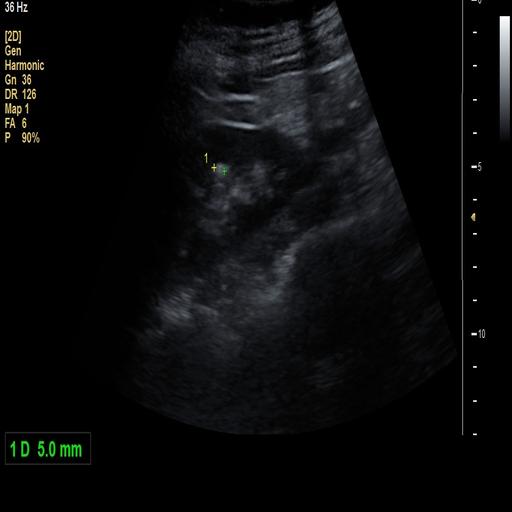

数据样例

结石肾脏样例